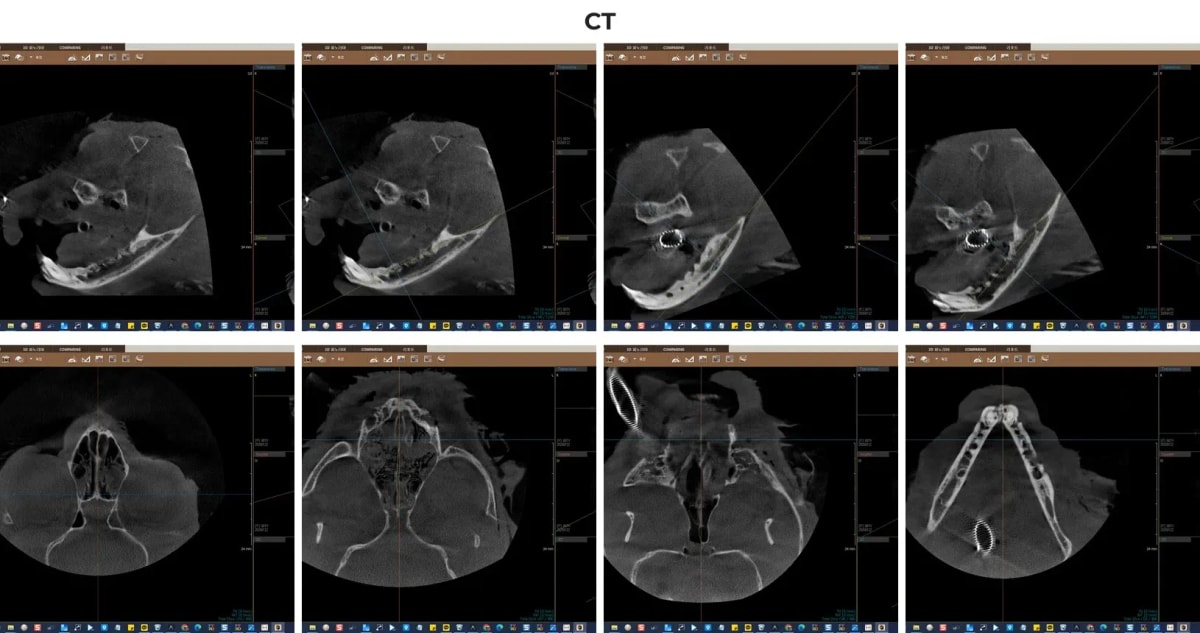

2. CT 진단의 중요성: 숨겨진 병변의 발견

육안으로 볼 때 필드의 입 안은 붉은 염증이 심하게 번져 있었지만, 정확히 어느 치아를 발치해야 할지 결정하기 위해서는 잇몸 아래의 뼈 상태를 확인해야 합니다. 일반적인 시진만으로는 치조골 흡수(잇몸뼈가 녹는 현상)의 정도나 뿌리의 기형 여부를 100% 파악하기 어렵습니다.

ℹ️ 치과 CT의 중요성

광주 전남 유일 동물전용 치과 CT는 3차원 영상을 제공하여, 일반 엑스레이에서 겹쳐 보이는 복잡한 상악골과 하악골 구조를 명확히 분리해 줍니다. 이를 통해 치근 분기부의 뼈 소실, 치아 흡수성 병변의 미세한 징후, 잔존 치근 등을 단 한 번의 촬영으로 정밀하게 진단할 수 있습니다.

치과 전용 CT를 통해 필드의 치주 질환 및 잇몸뼈 상태를 분석하는 화면